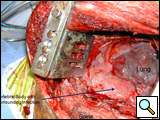

After completion of the spinal procedure, reorientation of the thoracic surgeon by the spinal surgeon is performed, including visualization of the implanted hardware and an explanation of the procedure that was performed (Figures 9a-c). Hemostasis is secured, the chest irrigated, and the posterior mediastinum is inspected for lymph leak (the presence of a CSF leak must be ruled out by the spine surgeon prior to this point in the operation). The diaphragm, if mobilized, is reattached to the fascia of the posterior chest wall with interrupted horizontal 0 prolene sutures or is anchored around the rib. A 28 Fr chest tube is placed in the posterior mediastinum and the chest is closed in a standard fashion. Postoperative spine imaging is necessary to demonstrate adequate position of the hardware and correction of the vertebral defect (Figures 10a-e, Video).

| Figure 9a: Resected vertebral body | Figure 9b: Prosthetic vertebral body placement | Figure 9c: Vertebral fixation plate |